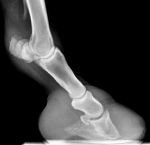

rtg2Na novějším snímku, tj. 21. 1., jsem naměřil úhel kopytní kosti 50° a úhel kopytního pouzdra ani ne 40°. To by bylo velké zhoršení (rotace o 10° je hranice se životem…), ale tady už spíše vidíme tzv. tureckou botu… tj. přírodní řešení (na snímcích není žádná nová rotace, protože tam není vzduchová komora po rotaci). Závěrem mohu říci, že lidské zásahy nepřinesly pozitivní změnu. Příroda sama by si pravděpodobně poradila lépe (turecká bota umožní návrat kopytní kosti do správné pozice).

Jako možný důvod neúspěšné léčby MVDr. Mach uvádí palmární bolestivost kopyta (koně jsou citliví na patky, krátí krok), kterou tato úprava vyvolává. Koně se nepohybují, nebo pouze leží. To u koně s chronickou laminitidou vede k tomu, že kost se z důvodu bolestivosti ,,nechce" vrátit do své správné pozice. Denali a její rentgeny jsou toho jasným důkazem.